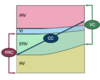

Which letter corresponds with the region where dead space is the greatest?

A

B

C

D

D

Explanation:

Dead space is ventilation without perfusion and shunt is perfusion without ventilation.

The graph examines the V/Q relationship in the entire lung.

Point C marks where ventilation and perfusion are equally matched.

Point D marks the region where ventilation is greater than perfusion; dead space is increased here.

Points A and B mark where perfusion exceeds ventilation; shunt is increased here.